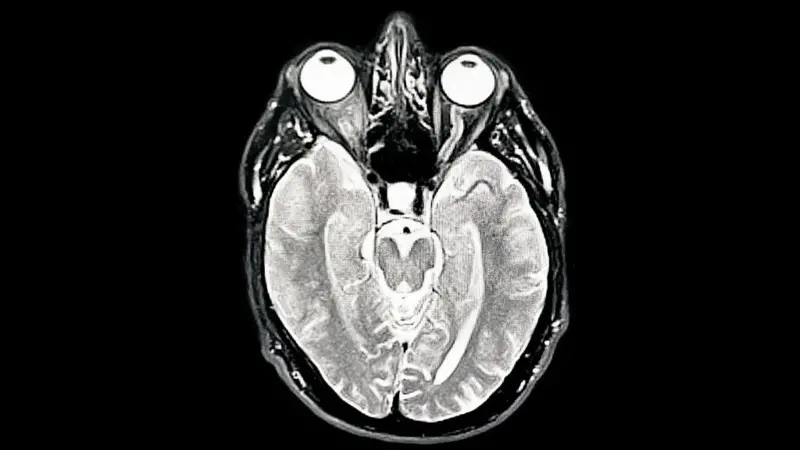

Un estudio de la Universidad de Cambridge que analizó alrededor de cuatro mil escáneres cerebrales hasta los 90 años redefinió las etapas de desarrollo cerebral. La investigación, publicada en Nature Communications, identificó cinco fases distintas a lo largo de la vida, revelando que la adolescencia cerebral se extiende hasta los 32 años. Estos hallazgos podrían explicar por qué el riesgo de trastornos mentales y demencia varía según la edad.